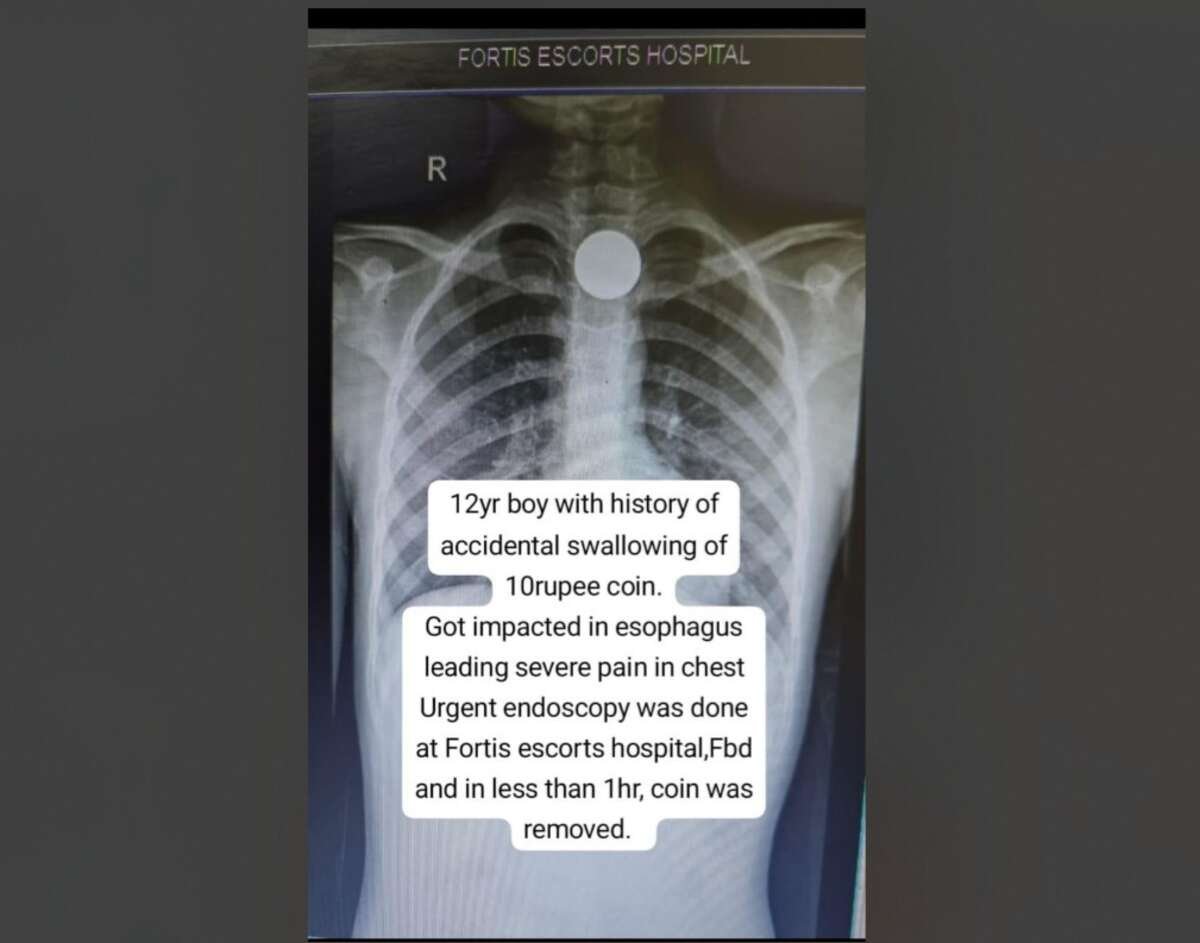

फरीदाबाद, 03 अक्टूबर, 2025: फोर्टिस एस्कॉर्ट्स फरीदाबाद के इमरजेंसी विभाग में इलाज के लिए 12-वर्षीय बच्चे को लाया गया था जिसने दुर्घटनावश ₹10 का सिक्का निगल लिया था। करीब 27 मिमी व्यास का यह सिक्का बच्चे की खाद्य नली (फूड पाइप) के ऊपरी हिस्से (अपर ईसोफैगस) में फंसा था और इस वजह से बच्चे की छाती में काफी दर्द था और उसे निगलने में भी परेशानी हो रही थी। अस्पताल में एक्स-रे जांच से फूड पाइप में सिक्के के फंसे होने की पुष्टि हुई। इलाज में देरी से जटिलताएं पैदा होने की आशंका थीं जो जीवनघातक भी हो सकती थीं, इसलिए डॉ निर्देश चौहान, कंसल्टेंट – गैस्ट्रोएंटेरोलॉजिस्ट, फोर्टिस एस्कॉर्ट्स फरीदाबाद के नेतृत्व में मेडिकल टीम ने तत्काल एंडोस्कोपी करने का फैसला किया ताकि मरीज को ईसोफैगल टियर्स, इंफेक्शन या सांस लेने में किसी प्रकार की कठिनाई न हो। मेडिकल टीम ने, बच्चे को अस्पताल पहुंचाने के आधे घंटे के भीतर ही, स्पेश्यलाइज़्ड एंडोस्कोपिक टूल्स की मदद से, सिक्के को बाहर निकालने में सफलता हासिल की। इस पूरी प्रक्रिया में लगभग 15 मिनट का समय लगा, और कुछ देर बाद ही बच्चे को अस्पताल से छुट्टी दे दी गई। फौलो-अप के बाद जांच से इस बात की पुष्टि भी हो गई कि ईसोफैगस को कोई नुकसान नहीं हुआ था।